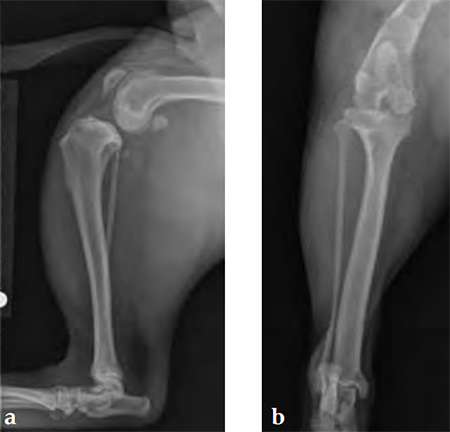

Case 2: Australian cattle dog

(Case provided by Brian Beale, Houston, USA)

An 8-year-old, female, spayed, 24 kg Australian cattle dog. This breed has short stocky legs and is very energetic and strong. The added strength of the 3.5 mm plate over the TPLO 2.7 mm plate was an advantage. The smaller head profile and shorter length of the TPLO 3.5 mm small stature plate allowed it to fit nicely on this patient.